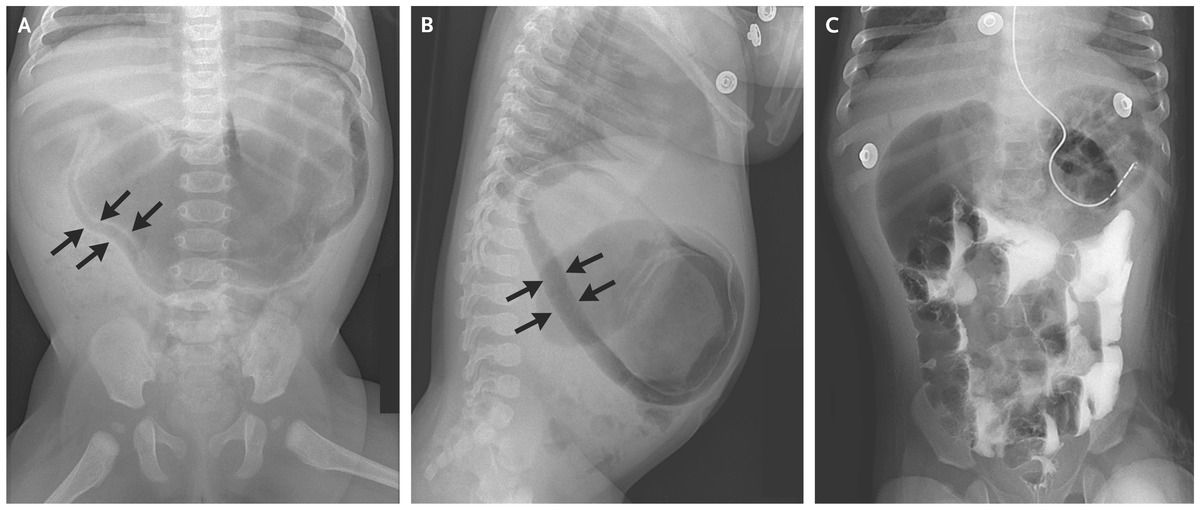

Laboratory investigations revealed a hypochloremic metabolic alkalosis, and radiographs showed gastric pneumatosis (Panels A and B, arrows).